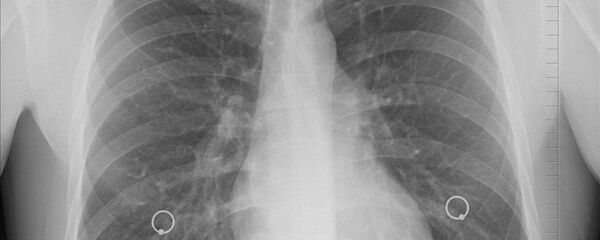

Au cours de l'expérience menée in vitro sur des cellules cancéreuses du poumon d’un homme et des cellules saines du poumon d’un singe, les chercheurs ont démontré que la cocarboxylase peut activer l’OGDC, diminuer la concentration en glutathion et ainsi empêcher les cellules cancéreuses de se propager. Cet effet a été observé seulement dans le cas de cellules atteintes par la maladie et la cocarboxylase n’affecte pas le taux de l’OGDC dans les cellules saines.